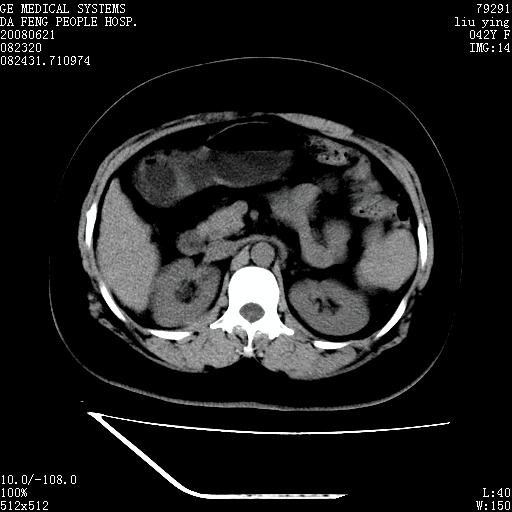

标题: CT14225:女性46岁。当地B超示肝内占位,来我院作CT检查。请 [打印本页]

标题: CT14225:女性46岁。当地B超示肝内占位,来我院作CT检查。请

速升速降,支持肝癌.脾体积增大,形态欠规整,请询问病史是否做过脾动脉栓塞.

速升速降,支持肝癌可能。

快进快出,符合肝癌表现-----------

肝内结节强化特点符合原发性肝癌表现,脾脏改变考虑为增大及先天发育所致。

动脉期病原灶明显强化高于肝密度且中央有无强化区,静脉期强化程度下降明显,延迟低于肝密度,考虑肝腺瘤可能性大,

肝内结节强化特点:快进快出符合原发性肝癌表现

此患者虽然符合快进的特点,却不符合快出的特点,因为门脉期几乎是等密度,不符合肝癌的增强表现,所以我考虑肝局灶性结节增生可能性大